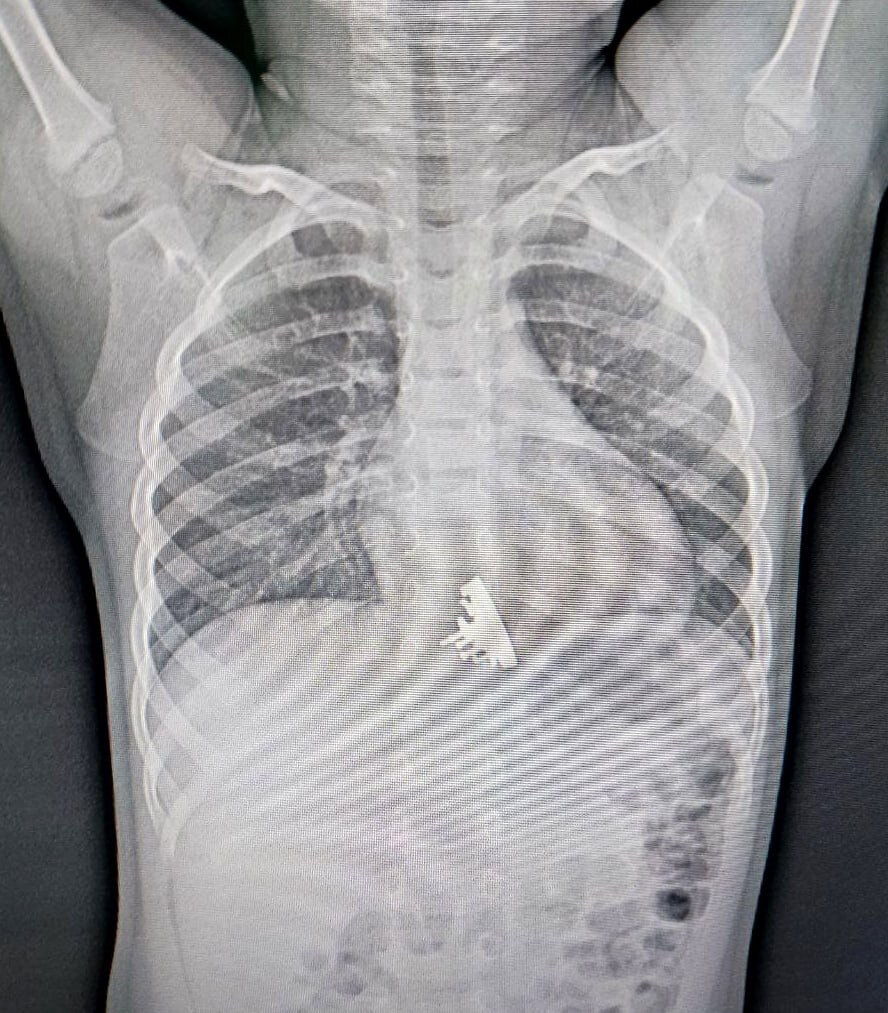

Игрушечный корабль был проглочен во время игры с конструктором. Родители заметили, что дочь поперхнулась, и забили тревогу. Рентген показал инородное тело в нижней трети пищевода. К делу подключили гастроскоп.

Извлечение «Авроры» заняло в два раза больше времени, чем извлечение, например, обычной монеты. Опасность заключалась в острых краях крейсера, которые могли серьезно повредить пищевод.